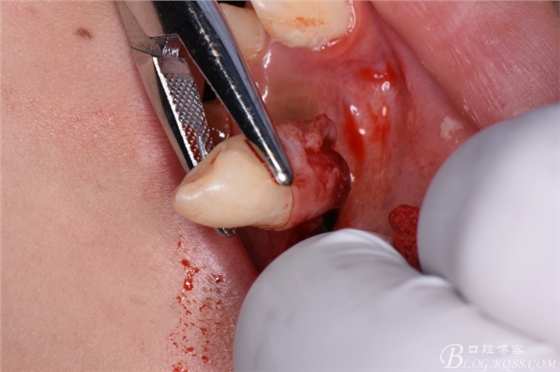

圖15.持針器取出23。

圖16.拔牙創(chuàng)口僅有23牙冠大小。

圖17.縫合兩針,創(chuàng)口小而整齊。